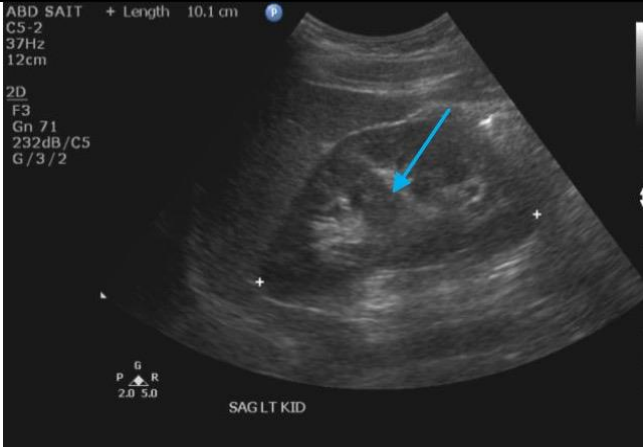

21

Q

Label the blue arrow

A

Left hypertrophied columns of bertin